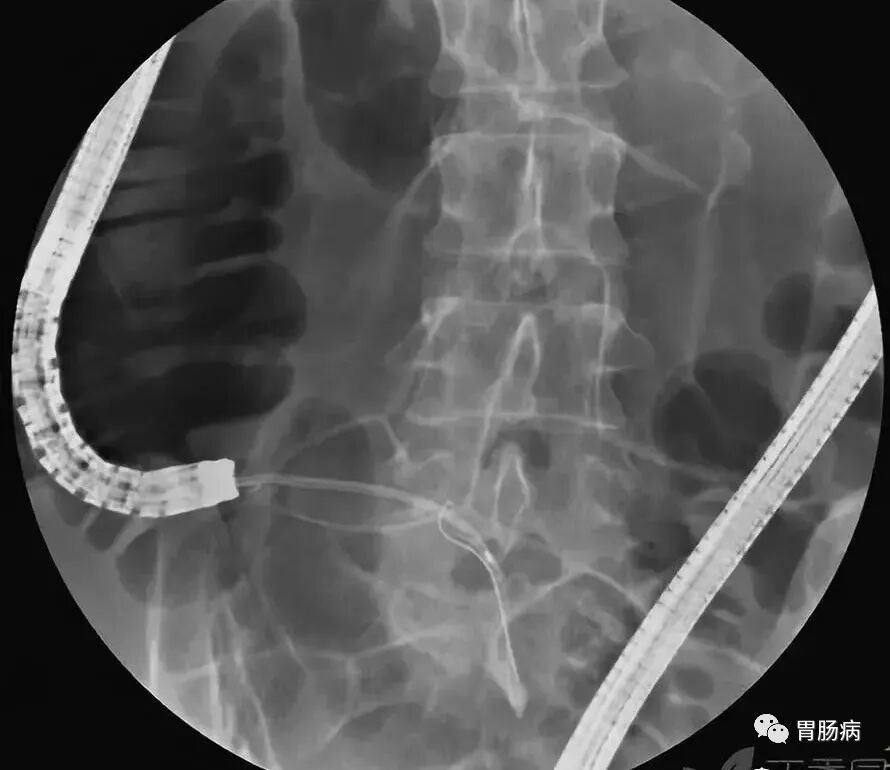

2、内镜逆行性阑尾造影术(endoscopic retrograde appendicography,ERA):

X线下,阑尾腔内注入造影剂显示阑尾腔的形态(椭圆形线圈),如有粪石(黑箭头),则行球囊取石术。并确认有无阑尾穿孔。